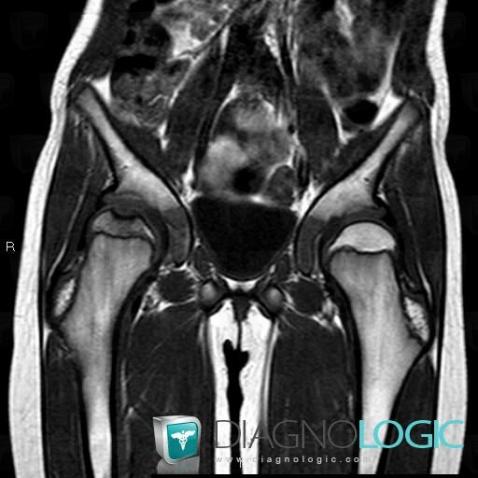

Ostéochondrite primitive-hanche, Fémur -supérieur, IRM

Voici les informations spécifiques à l'image clé ci dessus:

- Diagnostic Ostéochondrite primitive de hanche, Localisation(s) Fémur - 1/3 supérieur, comportant les gammes Lésion osseuse entourée d'œdème